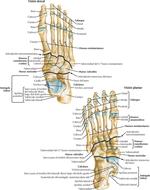

• Tarso y pie